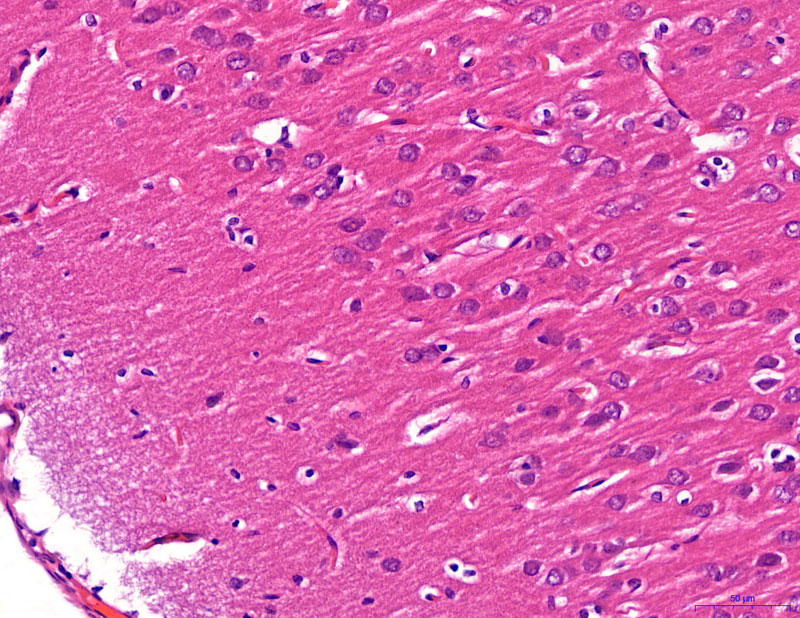

HE染色【組織病理染色】

正常-400